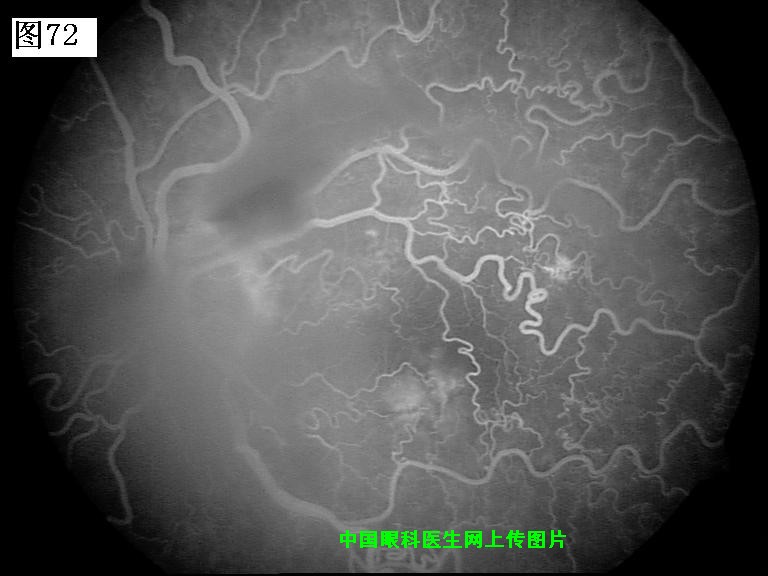

69 70 71 72